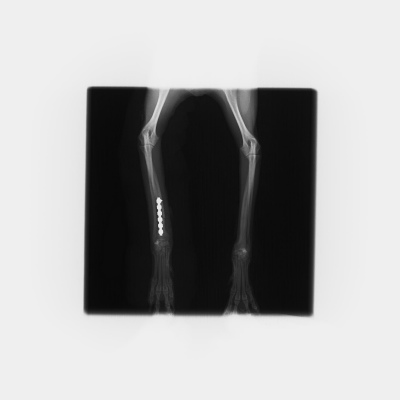

最初に紹介する写真は室内で転んで起きてしまった小型犬の橈尺骨(前足の骨)の骨折です。

骨折用の金属プレートを用いた手術によって、整復しました。